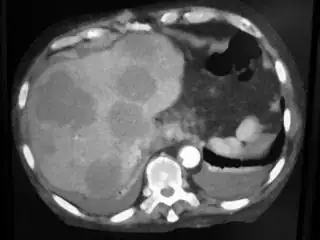

I am struggling in segmentation of images in matlab. My goal is to extract liver from ct scan images. This is sample image.

My problem is when I change image , rgb value of liver section may be different. Here is other sample image

Sample image 2.

For this image rgb value vary from 160 to 190 for each color component (r, g & b). Please help me to solve the problem.

Here is other sample image with rgb range varying from 110 to 180 sample image 3.